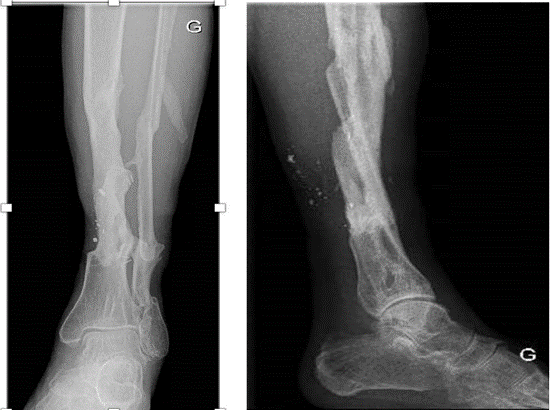

On clinical examination, the left lower limb was amputated almost completely over the entire middle 1/3 of the leg. However, a continuous posterior skin flap of 1/8th of the periphery of the leg was present (Figures 1-17). Distal pulses were absent, and the distal segment was cold. Neurological assessment was not possible at this stage.

Figure 2 : X-ray imaging shows a multifragmented fracture of the tibia and fibula.